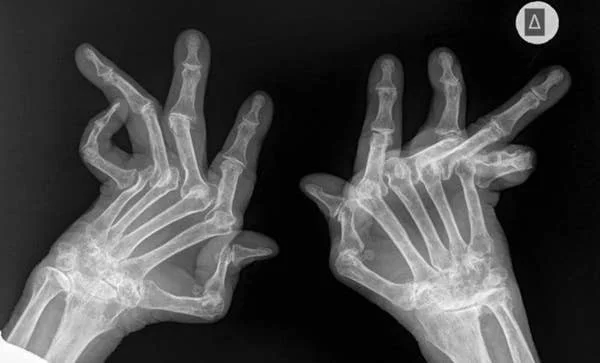

Ревматоидный артрит — это серьезное заболевание.